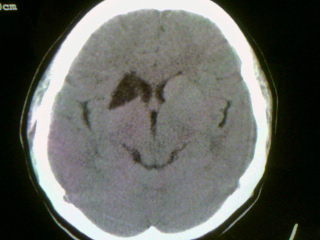

以下是引用wwh40在2009-3-30 17:48:00的发言:[br]右侧基底节区(侧脑室前角旁)可见一三角形低密度影,ct值不详(水样或脂肪密度?),相邻侧脑室较对侧侧脑室前角扩大,[br]意见:1.如果是水样密度,结合上述特点,考虑脑软化灶。[br] 2.如果是脂肪密度,考虑脂肪瘤可能。[br]